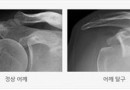

어깨의 탈구

견관절 재발성 탈구란? 격렬한 운동이나 외상으로 인하여 어깨가 빠지게 되면 어깨 전하방의 인대가 늘어나거나 파열이 발생하게 되면서 반복적으로 관절의 이완이나 탈구가 발생하게 되는 병입니다. 젊은 연령에서 어깨가 빠지게 되면 60~70%에서 탈구가 재발하게 되고 또…

어깨 탈구의 치료

견관절 탈구가 반복적으로 발생하게 되면 관절 주변의 인대가 늘어나고 주변의 인대에도 손상을 가져올 수 있으므로 수술적 봉합술이 필요합니다. 일반적으로 관절경 수술로 치료가 가능하며 파열된 관절 와순을 봉합해주고 늘어난 관절낭을 복원하게 됩니다. 수술 후 관리 및…